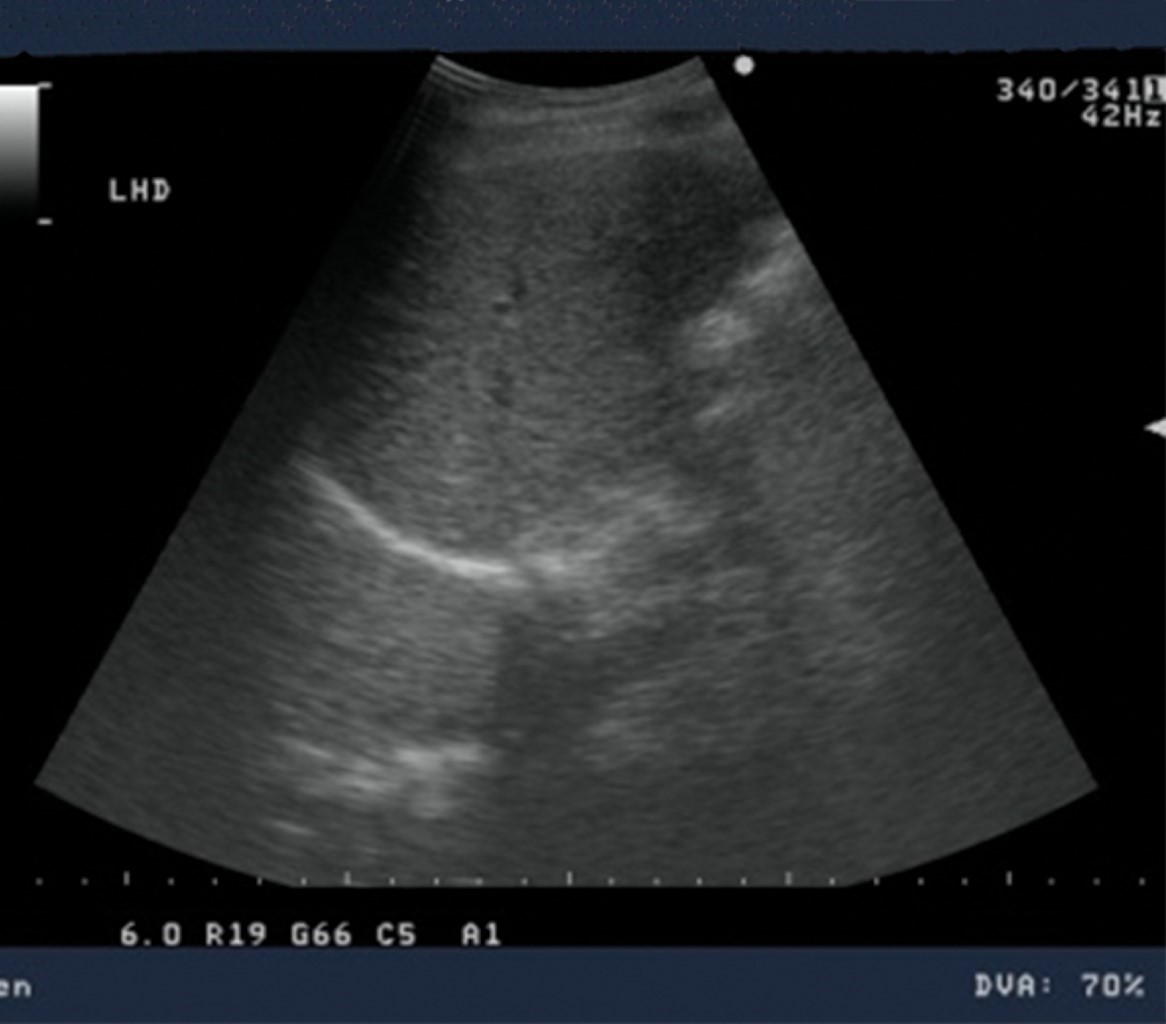

USG of the liver and biliary tract was performed on admission, reporting a heterogeneous parenchymal liver gland with hypoechoic image, poorly defined borders, diameters of 6.37 × 5.23 cm located in segment VI, heterogeneous, with poor vascularity suggestive of hepatic abscess vs. hepatocarcinoma, preserved portal vessels, intrahepatic ducts with air inside suggestive of pneumobilia, common bile duct and portal vein of normal caliber. Laboratory one day after admission with glucose 86 mg/dl, urea 17 mg/dl, BUN 7.9 mg/dl, Ca 6.9 mg/dl, GGT 349 U/l, BD 3.34 mg/dl, BI 1.29 mg/dl, BT 4.63 mg/dl, FA 410 U/l, AST 37 U/l, ALT 28 U/l, DHL 131 U/l, Na 134 mmol/l, K 3.7 mmol/l, CL 108 mmol/l, leukocytes 13.3 × 103/μl, neutrophils 85.1%, HB 10.4 g/dl, OHT 30.2%, PLT 220 × 103/μl, PT 15.6 sec, PTT 34.7 sec, INR 1.16.